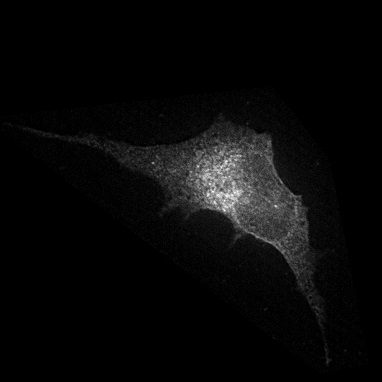

Microscopy techniques are employed to capture subcellular localization images of proteins in a cell, which were previously analyzed using traditional wet methods. However, advances in microscopy techniques have brought an avalanche of medical images in a considerable amount; hence, manual analysis and processing of these medical images become nearly impossible for biologists. Moreover, a subjective inspection of images may lead to errors in decision-making process shao2017deep ; tahir2011protein ; kreft2004automated . It is highly likely that the images generated for proteins of the same class may look visually different (see Figure 1). Similarly, proteins belonging to two different classes may look alike. Such a situation leads to the poor performance of classification systems. These problems are resolved by applying different hand-crafted feature extraction strategies to capture multiple views from the same image tahir2016protein . Hence, this is a cumbersome job and may fail to discriminate with high accuracy.

Prediction confidence: We compare the prediction confidence of traditional classifiers trained on Yeast and HeLa datasets against our PLCNN on four images as shown in Figure 11. Each image has the prediction probabilities for each algorithm underneath. The red color shows when the prediction is incorrect, whereas the green is for the correct outcome. It can be observed that our method predicts the correct labels with high confidence, while the probability is very low when the prediction is incorrect. The image in the first column in Figure 11 is very challenging due to minimum texture and almost no structure. All the methods failed to identify the type of protein in the mentioned image correctly. However, the competing methods prediction scores are much higher than ours. Similarly, our algorithm confidence is always high when the prediction is correct and low when it is incorrect. This shows the learning capability of our network.

![]() |

|

| AlexNet | 0.32 | 0.57 | 0.79 | 0.82 |

|---|---|---|---|---|

| ResNet | 0.69 | 0.68 | 0.49 | 1 |

| DenseNet | 0.60 | 0.79 | 0.75 | 0.90 |

| PLCNN | 0.26 | 0.88 | 1 | 1 |